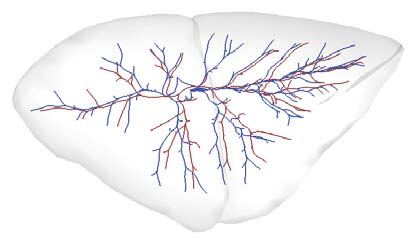

Recent advances in imaging techniques have enabled us to visualize lung tumors or nodules in early-stage cancer. However, the positions of nodules can change because of intraoperative lung deflation, and the modeling of pneumothorax-associated deformation remains a challenging issue for intraoperative tumor localization. In this study, we introduce spatial and geometric analysis methods for inflated/deflated lungs and discuss heterogeneity in pneumothorax-associated deformation. Contrast-enhanced CT images simulating intraoperative conditions were acquired from live Beagle dogs. Deformable mesh registration techniques were designed to map the surface and subsurface tissues of lung lobes. The developed framework addressed local mismatches of bronchial tree structures and achieved stable registration with a Hausdorff distance of less than 1 mm and a target registration error of less than 5 mm. Our results show that the strain of lung parenchyma was 35% higher than that of bronchi, and that subsurface deformation in the deflated lung is heterogeneous.